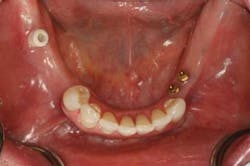

In this case, we wanted to replace the crowns on teeth Nos. 8 and 9. As you can see in the nonretracted before photos (Figs. 1 and 2), the patient had two preexisting high value PFMs. When you look at the condition of the gingiva in the before, was this possibly a base metal allergy? This helped with my decision to go with BruxZir all-ceramic crowns.

In the retracted view (Figs. 3 and 4), you can see the full extent of the gingival issues. As I placed the topical on tooth No. 9 with a cotton swab, it started to bleed. You can see that the midline on the existing crown is off, as are the axial inclinations of the two crowns. The unhealthy gingival tissue was removed with a diode laser and BioTemps were placed.